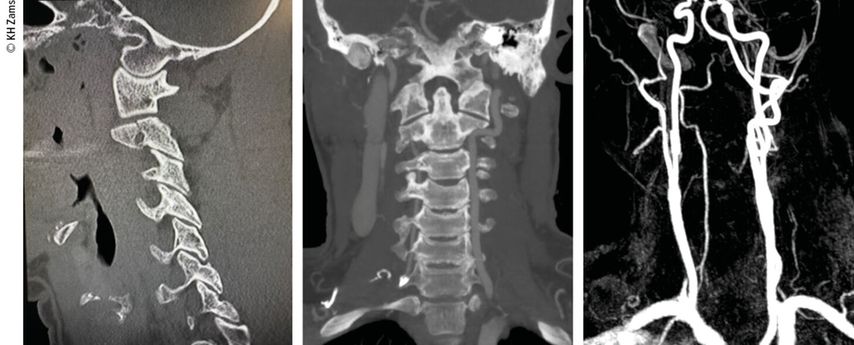

Abb. 2: Fallbeispiel: Mann, 57a, Z.n. Fahrradsturz, stabile Fraktur des Proc. artic. C2 r. mit Dissektion der A. vertebralis r. mit asymptomatischem Substanzdefekt im hinteren Stromgebiet (cMRT), Heparintherapie initial, anschließend APT